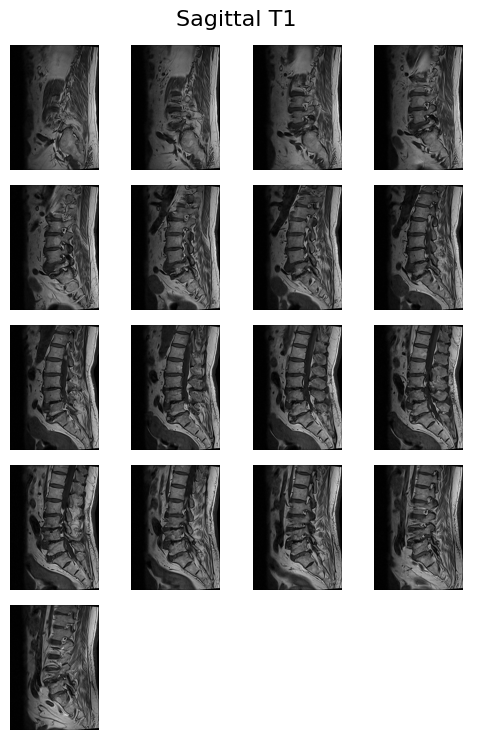

4. Hiển thị ảnh MRI của một bệnh nhân

Truy xuất meta thông tin của một bệnh nhân

patient = train.iloc[1]

ptobj = meta_obj[str(patient['study_id'])]

print(ptobj){

'folder_path': '/kaggle/input/rsna-2024-lumbar-spine-degenerative-classification/train_images/4646740',

'SeriesInstanceUIDs': ['3666319702', '3486248476', '3201256954'],

'SeriesDescriptions': ['Sagittal T2/STIR', 'Sagittal T1', 'Axial T2']

}- folder_path: Thư mục chứa ảnh MRI của bệnh nhân.

- SeriesInstanceUIDs: Danh sách các series (bộ ảnh) cho các kiểu chụp/mặt phẳng khác nhau.

- SeriesDescriptions: Mô tả từng series (ví dụ: Sagittal T2/STIR, Sagittal T1, Axial T2). Đưa dữ liệu ảnh vào cấu trúc dễ thao tác

for i in im_list_dcm:

display_images([x['dicom'].pixel_array for x in im_list_dcm[i]['images']],

im_list_dcm[i]['description'])- Chức năng: Hiển thị các ảnh MRI (dạng lát cắt) cho từng series theo mô tả (ví dụ: “Sagittal T2/STIR”).

- Mỗi lần lặp sẽ hiện toàn bộ ảnh lát cắt của một series (tối đa 4 ảnh trên mỗi hàng, tự động xuống hàng).